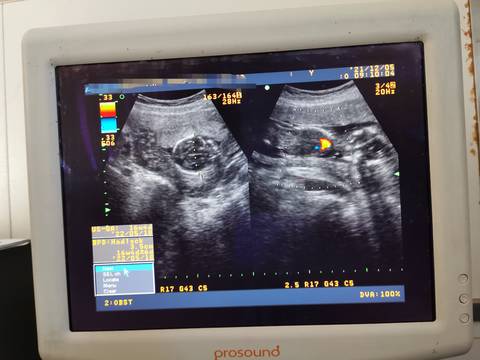

医生说小宝很明显 这是男孩还是女孩,反正我啥都没看到

小吴的小仙 2021-12-05 22:15

其实通过这些是看不出来的,而且也不准确,在怀孕期间不要想太多,我觉得只要宝宝发育好的话就可以。

亲,我们都是一样觉得好奇,确实没什么依据,不要想太多,生下来最准确的,一切顺利!

不会看,估计只有医生懂